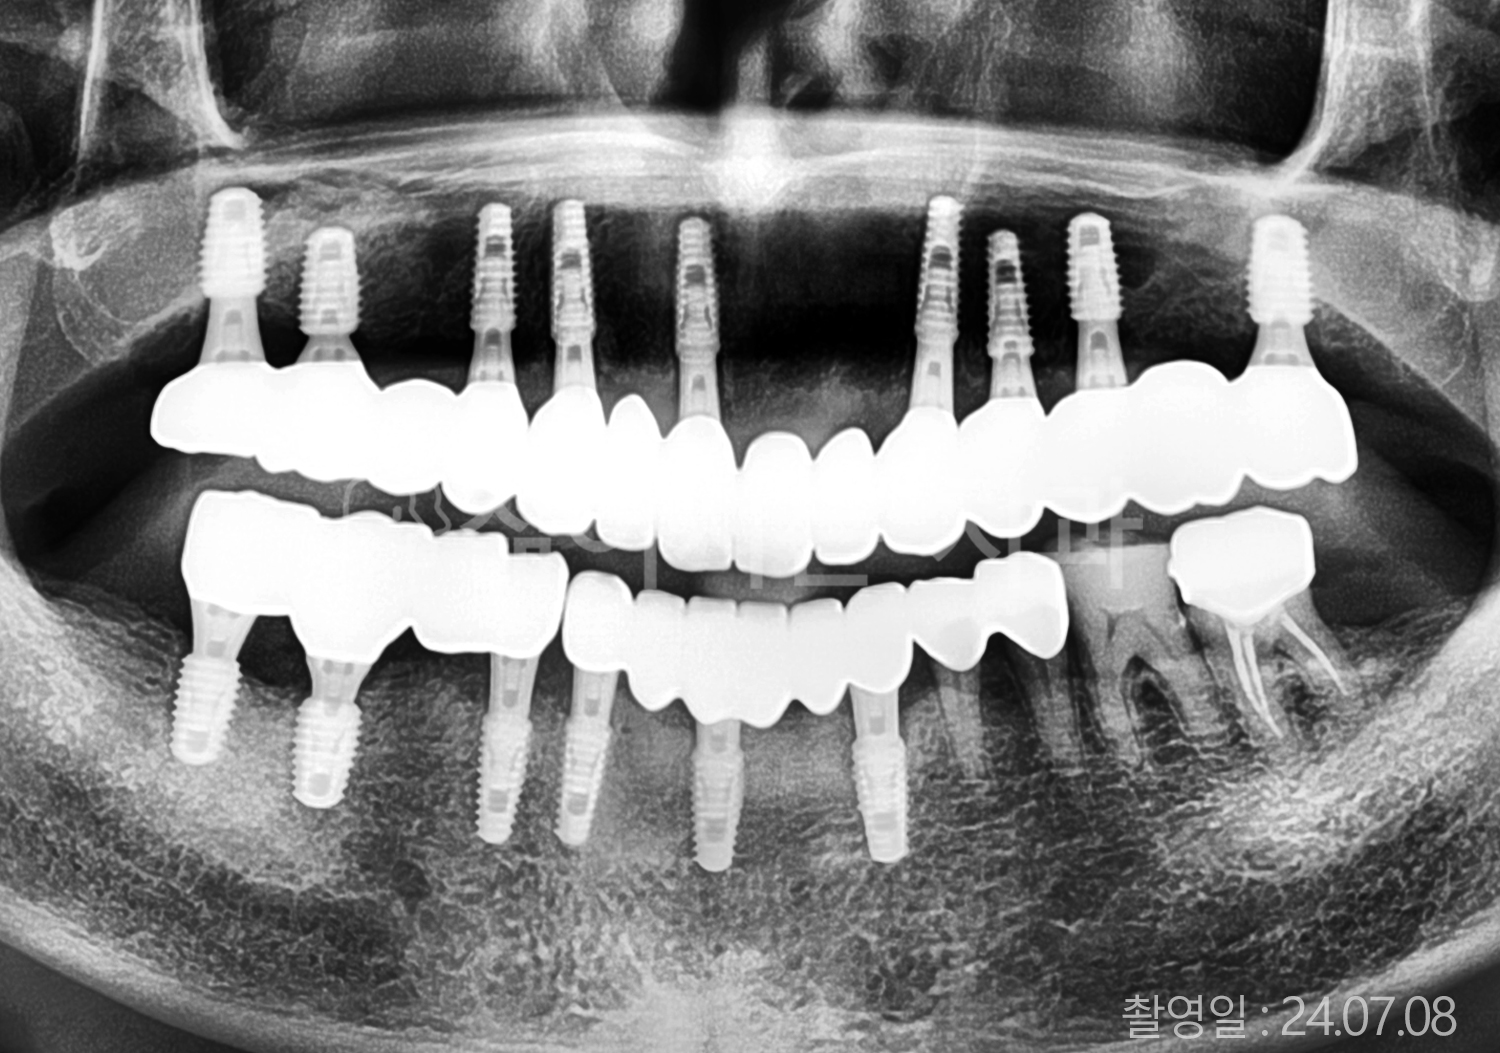

치료사례(치아)

• 80대 전체치아 10개 이상 임플란트

• 60대 고혈압, 당뇨, 고지혈증 전체치아 10개 이상 임플란트

• 60대 전체치아 10개 이상 임플란트

• 60대 고혈압, 고지혈증 전체치아 10개 이상 임플란트

• 50대 고혈압, 당뇨, 고지혈증 전체치아 10개 이상 임플란트

• 70대 골다골증, 파킨스병 전체치아 10개 이상 임플란트

• 40대 전체치아 10개 이상 임플란트

• 60대 골다골증 전체치아 10개 이상 임플란트

• 40대 고혈압 전체치아 10개 이상 임플란트

• 50대 전체치아 10개 이상 임플란트

• 70대 전체치아 10개 이상 임플란트

위 사진의 저작권은 젊어지는 치과에 있습니다.

본 사진은 환자분의 동의 하에 게재 되었습니다.

* 위 사진은 동일 조건에서 촬영 되었습니다. / 모든 치료에는 부작용이 발생할 수 있습니다.